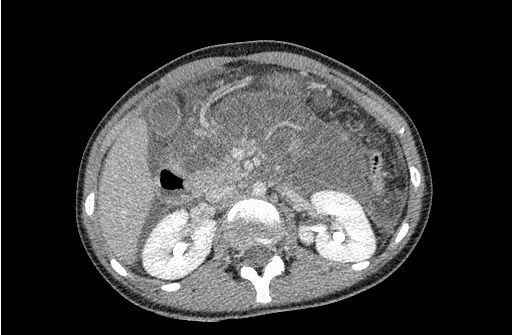

Przypadek 6: 14-latka skierowana z Izby Przyjęć z powodu bólu brzucha w nadbrzuszu.

Rozpoznanie: W badaniu usg - trzustka pogrubiała, obrzęknięta (strzałki), przewód trzustkowy nieposzerzony (dla porównania na zdjęciu w górnym prawym rogu - prawidłowa trzustka u innego pacjenta). W badaniu TK (poniżej) - trzustka powiększona, niejednorodna, słabo odgraniczona od otoczenia, po podaniu kontrastu jedynie głowa fragmentarycznie na wysokości wyrostka haczykowatego ulega wzmocnieniu kontrastowemu, pozostały miąższ trzustki pozostaje hypodensyjny. Obraz ostrego martwiczego zapalenia trzustki.